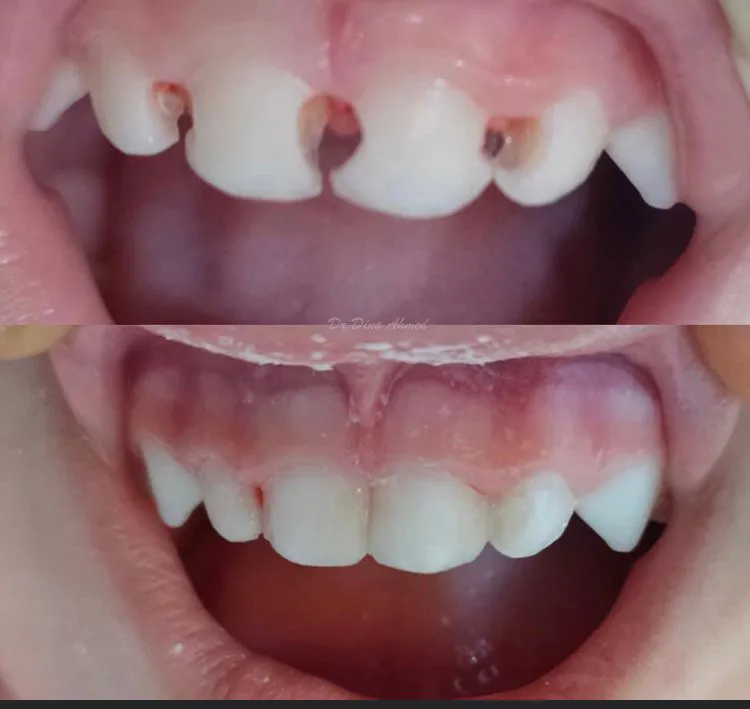

Children